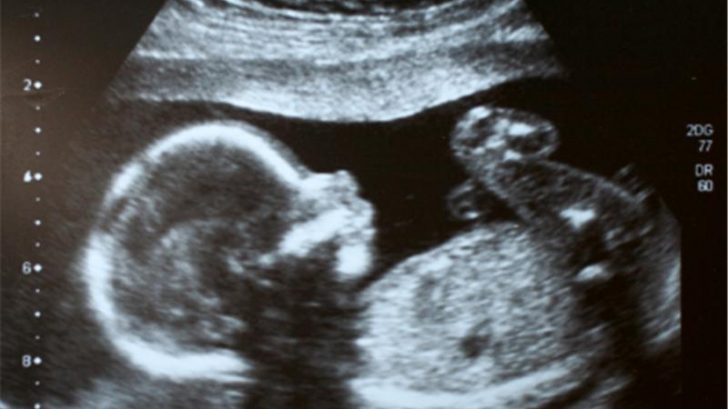

V první fázi umělého oplodnění je žena stimulována hormony, aby v jejím těle dozrál dostatečný počet vajíček. Zralá vajíčka jsou pak odebrána při krátkodobé narkóze, ve stejné době muž dodá sperma.

Další postup je v režii embryologa. Po splynutí vajíček a spermií jsou vzniklá embrya několik dnů kultivována v laboratoři a pak zavedena ženě do dělohy. Implantuje se většinou jedno až dvě embrya, nepoužitá embrya mohou být zamražena a uschována pro další cyklus. Existují různé způsoby oplodnění, záleží na konkrétním zdravotním stavu páru.